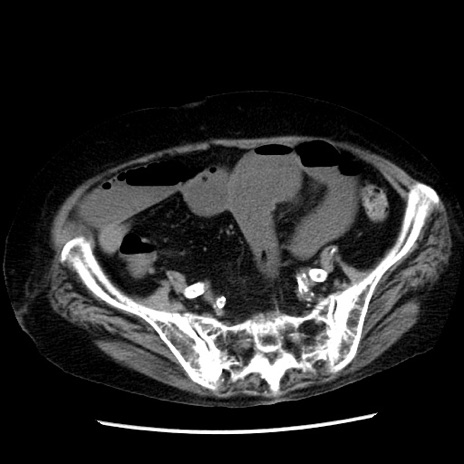

症例14(横断像)

【症例】 90歳代女性

【主訴】 腹痛・嘔吐

【現病歴】今朝から左側腹部痛を認めた。 経過観察していたが、嘔吐を認めたため来院。

【既往歴】 子宮癌術後

【身体所見】 意識清明、BP 127/54mmHg、P 98bpm Sp02 95%(RA)、BT 35.8°C、腹部平坦・軟腸ぜん動音聴取良好、右下腹部圧痛(+) 反跳痛なし

【データ】WBC 9800、CRP 0.46